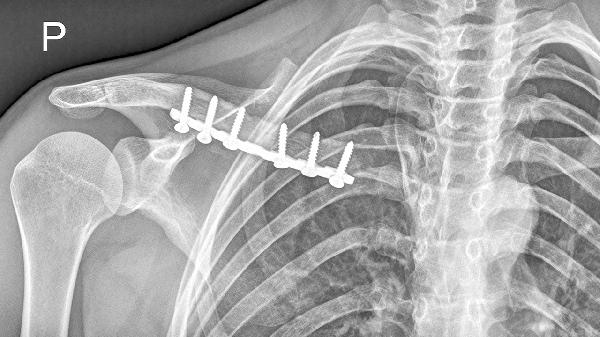

低血糖是否可以进行锁骨手术,主要取决于低血糖的严重程度和患者的整体健康状况。如果患者出现严重的低血糖症状,例如心慌、手抖,甚至有昏迷风险,那么进行手术是不建议的。这种情况下,首先需要通过补充含糖食物或药物来稳定血糖水平,确保身体状态稳定后才能考虑手术。而如果低血糖症状较轻,患者身体状态良好,没有其他严重的健康问题,通常在医生的指导下可以选择适当的时机进行手术。

2、可以手术的情况:如果患者的低血糖症状相对轻微,仅仅表现为轻度的头晕或眼花,并且患者没有其他基础疾病,身体条件良好,那么在医生评估后,可以在血糖稳定的情况下进行手术。手术前,医生会根据患者的具体情况调整手术方案,以确保安全。